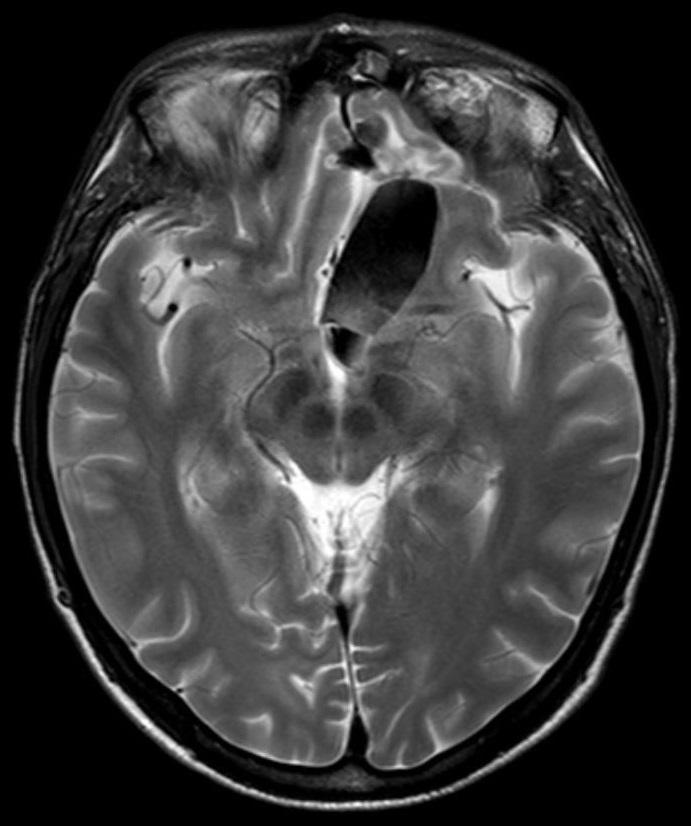

Een 41-jarige man komt na een tonisch-clonisch insult op de SEH. Vlak voor het insult heeft hij vieze smaak- en geursensaties en een licht, onwerkelijk gevoel in het hoofd gehad. 23 jaar geleden heeft hij zijn linker oog verloren bij een auto-ongeluk. Het neurologisch onderzoek is niet-afwijkend.